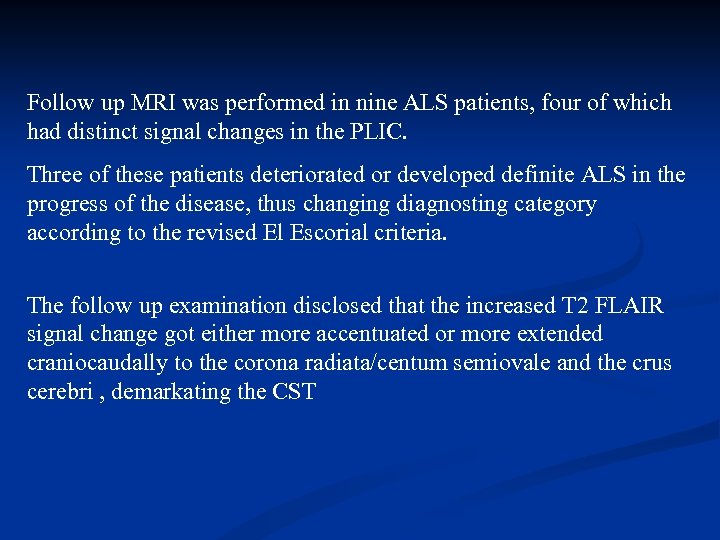

Follow up MRI was performed in nine ALS patients, four of which had distinct signal changes in the PLIC. Three of these patients deteriorated or developed definite ALS in the progress of the disease, thus changing diagnosting category according to the revised El Escorial criteria. The follow up examination disclosed that the increased T 2 FLAIR signal change got either more accentuated or more extended craniocaudally to the corona radiata/centum semiovale and the crus cerebri , demarkating the CST

Follow up MRI was performed in nine ALS patients, four of which had distinct signal changes in the PLIC. Three of these patients deteriorated or developed definite ALS in the progress of the disease, thus changing diagnosting category according to the revised El Escorial criteria. The follow up examination disclosed that the increased T 2 FLAIR signal change got either more accentuated or more extended craniocaudally to the corona radiata/centum semiovale and the crus cerebri , demarkating the CST